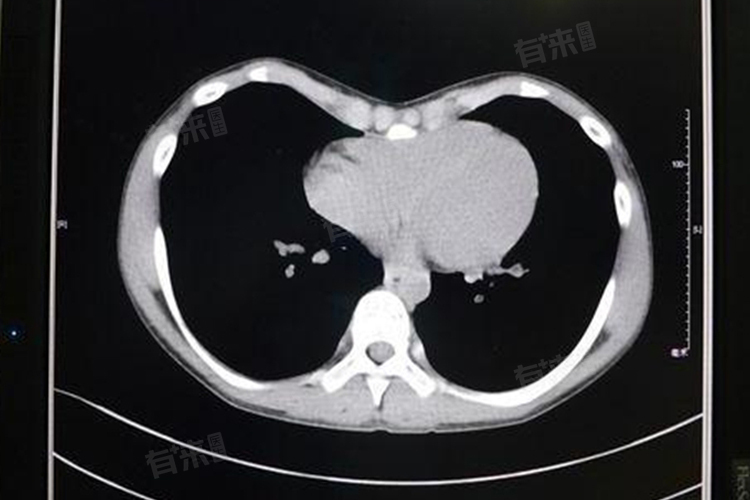

女性胸部CT是一种重要的医学影像检查技术,能够详细展现胸部内部结构,帮助医生准确诊断多种疾病,比如乳腺疾病、肺部疾病、纵隔与胸腔疾病等。

- 肺部炎症:如肺炎,胸部CT能够清晰显示肺部炎症的范围、程度以及是否伴有胸腔积液等,为治疗方案的制定提供依据。

- 肺部肿瘤:胸部CT能够检测到肺部结节、肿块等异常表现,有助于诊断肺癌等恶性肿瘤。

- 肺部栓塞:胸部CT能够发现肺动脉内的血栓或异物,为肺部栓塞的诊断提供有力支持。

- 纵隔肿瘤:胸部CT能够清晰显示纵隔区域内的肿瘤,包括淋巴瘤、胸腺瘤等,为治疗方案的制定提供关键信息。

- 胸腔积液:胸部CT能够准确测量胸腔积液的量,并判断其性质,有助于诊断胸膜炎、肺部肿瘤等引起的胸腔积液。

- 气胸:胸部CT能够清晰显示胸膜腔内的气体积聚,为气胸的诊断和治疗提供重要依据。